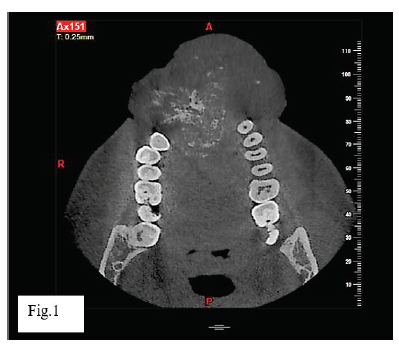

Diagnostic imaging demonstrated an expansile soft tissue shadow associated with and displacing the right central and lateral incisors (Figure 2). Cone-beam computed tomography revealed mild maxillary superficial cortical erosion in the anterior maxilla with solid, linear and scattered foci of radiopacity evident intralesionally. Histopathological examination of the excised tumour, supported by radiological interpretation, confirmed microscopic features of a giant peripheral ossifying fibroma with a myxoid component.

While peripheral ossifying fibromas are not uncommon, this case demonstrates several less frequently evidenced features. Firstly, the dimensions of this lesion exceed those most frequently reported in the literature and make this case additive to the limited proportion of peripheral ossifying fibromas described as large, atypical or gigantiform.1,2,4,5 Secondly, cone-beam computed tomography demonstrated localised superficial erosion of the proximal maxillary alveolar bone with the displacement of the right central and lateral incisors. Intralesional soft tissue shadows demonstrated significant amounts of radiopaque material arranged in a solid mass with band-like extensions and scattered foci. There is marked displacement of the maxillary right incisors. Bilaterally the maxillary canines demonstrate widened periodontal ligament spaces. Radiographic findings within peripheral ossifying fibromas are infrequent and have been cited to occur in less than 10% of lesions.2 The significant amount and appearance of mineralisation evident radiographically, in this case, may be attributed to the maturation of the lesion and correlates to a history of long duration. This case highlights for the clinician the exuberant mineralisation that may uncommonly be evident radiographically in peripheral ossifying fibromas.